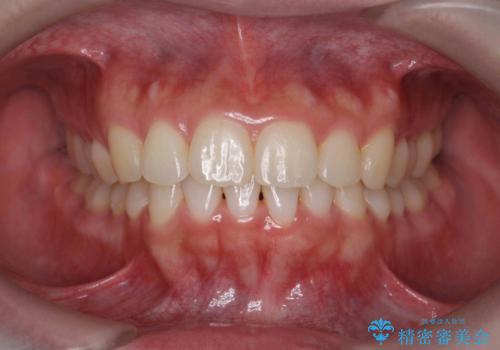

![[ インビザライン矯正 ] マウスピース矯正で治す、前歯のガタつきの症例 治療前](https://seimitsushinbi.jp/wp/wp-content/uploads/2022/02/324533f54aaa29eca08b0a9fdd3af7e2-500x350.jpg?v=1644473292)

![[ インビザライン矯正 ] マウスピース矯正で治す、前歯のガタつきの症例 治療後](https://seimitsushinbi.jp/wp/wp-content/uploads/2022/02/IMG_1698-500x350.jpg?v=1644473356)